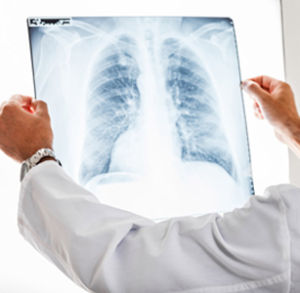

圖像特點

CT圖像CT圖像是由一定數目由黑到白不同灰度的像素按矩陣排列所構成。這些像素反映的是相應體素的X射線吸收係數。不同CT裝置所得圖像的像素大小及數目不同。大小可以是1.0×1.0mm,0.5×0.5mm不等;數目可以是256×256,即65536個,或512×512,即262144個不等。顯然,像素越小,數目越多,構成圖像越細緻,即空間分辨力(spatial resolution)高。CT圖像的空間分辨力不如X射線圖像高。

CT圖像是以不同的灰度來表示,反映器官和組織對X射線的吸收程度。因此,與X射線圖像所示的黑白影像一樣,黑影表示低吸收區,即低密度區,如含氣體多的肺部;白影表示高吸收區,即高密度區,如骨骼。但是CT與X射線圖像相比,CT的密度分辨力高,即有高的密度分辨力(density resolutiln)。因此,人體軟組織的密度差別雖小,吸收係數雖多接近於水,也能形成對比而成像。這是CT的突出優點。所以,CT可以更好地顯示由軟組織構成的器官,如腦、脊髓、縱隔、肺、肝、膽、胰以及盆部器官等,並在良好的解剖圖像背景上顯示出病變的影像。

CT圖像是層面圖像,常用的是橫斷面。為了顯示整個器官,需要多個連續的層面圖像。通過CT設備上圖像的重建程式的使用,還可重建冠狀面和矢狀面的層面圖像,可以多角度查看器官和病變的關係。

CT由於CT的高分辨力,可使器官和結構清楚顯影,能清楚顯示出病變。在臨床上,神經系統與頭頸部CT診斷套用早,對腦瘤、腦外傷、腦血管意外、腦的炎症與寄生蟲病、腦先天畸形和腦實質性病變等診斷價值大。在五官科診斷中,對於框內腫瘤、鼻竇、咽喉部腫瘤,特別是內耳發育異常有診斷價值。

在呼吸系統診斷中,對肺癌的診斷、縱隔腫瘤的檢查和瘤體內部結構以及肺門及縱隔有無淋巴結的轉移,做CT檢查做出的診斷都是比較可靠的。